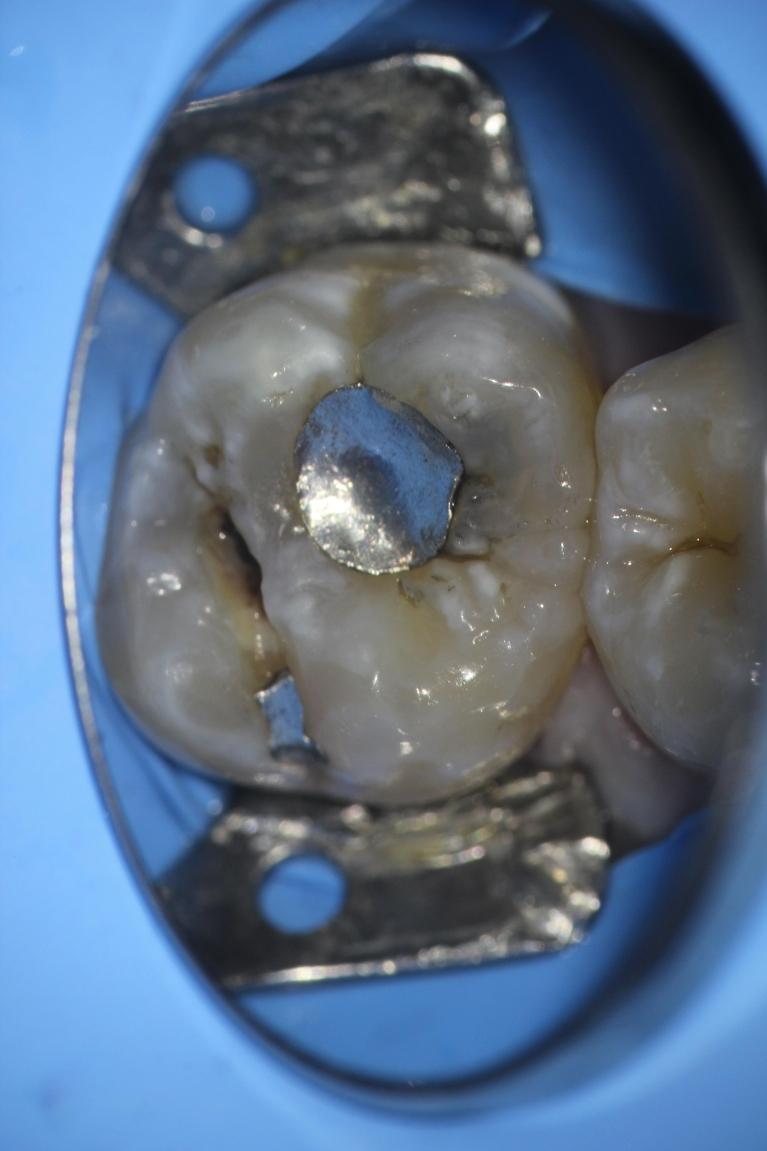

Welcome to our smile gallery, where you can browse photos of some of our best work. We hope that you find inspiration here for what is possible for your own smile. If you are considering cosmetic dentistry or you need help getting on track with your oral health, we look forward to hearing from you.

In the meantime, enjoy our before-and-after photos. We look forward to providing you with the same exceptional results.